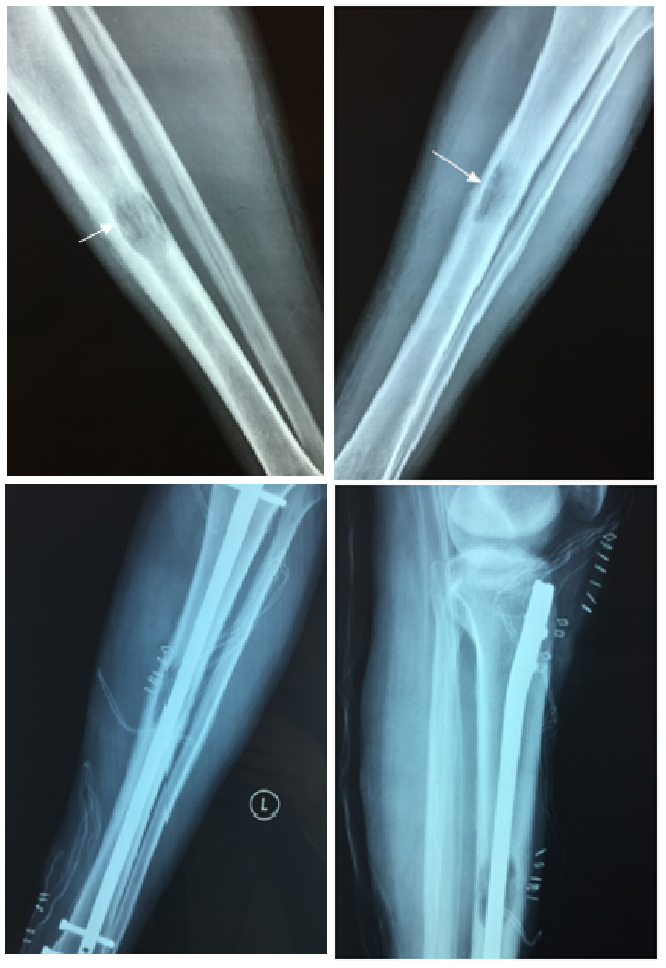

Unusual Tibial Site Metastases from a Muscle Invasive Urothelial Carcinoma: A Rare Case Report

Kastanis G., Bachlitzanaki M., Pantouvaki A., Magarakis G., Spyrantis M.

International Journal of Innovative Research in Medical Science·September 2, 2020